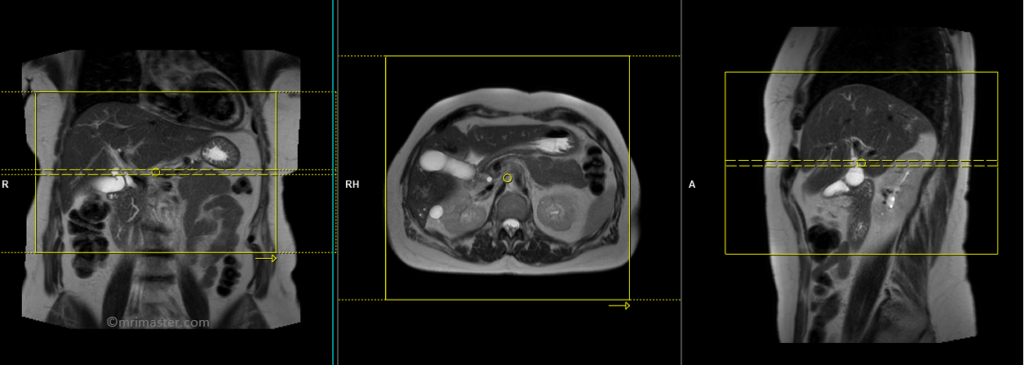

T2 HASTE 5 mm breath hold axial

Plan the axial slices on the coronal breath hold images and position the block horizontally across the liver as shown. Verify the positioning in the other two planes. Establish an appropriate angle in the sagittal plane, aligning it horizontally across the liver. The slices must be sufficient to cover the entire liver from the diaphragm down to the C loop of the duodenum. The phase direction should be from right to left to minimize ghosting artifacts from the anterior abdominal wall. Use phase oversampling to prevent wrap-around artifacts. Instruct the patient to hold their breath during image acquisition. (In our department, we typically instruct patients to take two breaths in and out before providing the “breathe in and hold” instruction.)

TR 2500-3000 | TE 90-110 | FLIP 130 | NEX 1 | SLICE 5MM | MATRIX 256×256 | FOV 350 | PHASE R>L | OVERSAMPLE 50% | TRIGGER NO |